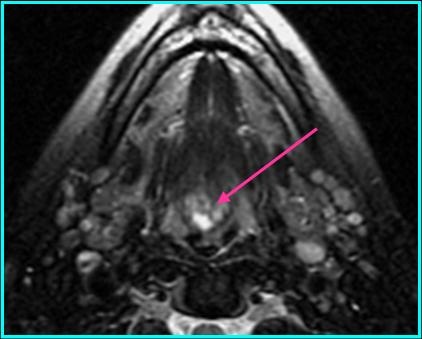

Radiologic Findings

- On MR: high signal with T1 and T2 when compared to muscle; enhancement on T1 post-contrast